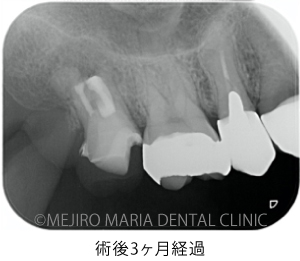

上記のエックス線写真で、術直後に根尖付近に見られた透過像(黒く見える部分)は、3ヶ月後には小さくなり、治癒傾向にあることが確認できます。また、術前に見られた歯周ポケットの改善と瘻孔(フィステル)の消失も確認できます。

歯質が少ない状態ではありますが、術後3ヶ月経過した時点で違和感の消失、病的な歯周ポケットの改善、瘻孔(フィステル)の消失が確認でき、経過は良好です。最終補綴(被せもの)へ移行後も、最低2年間は年1回ほどの経過観察を予定しています。